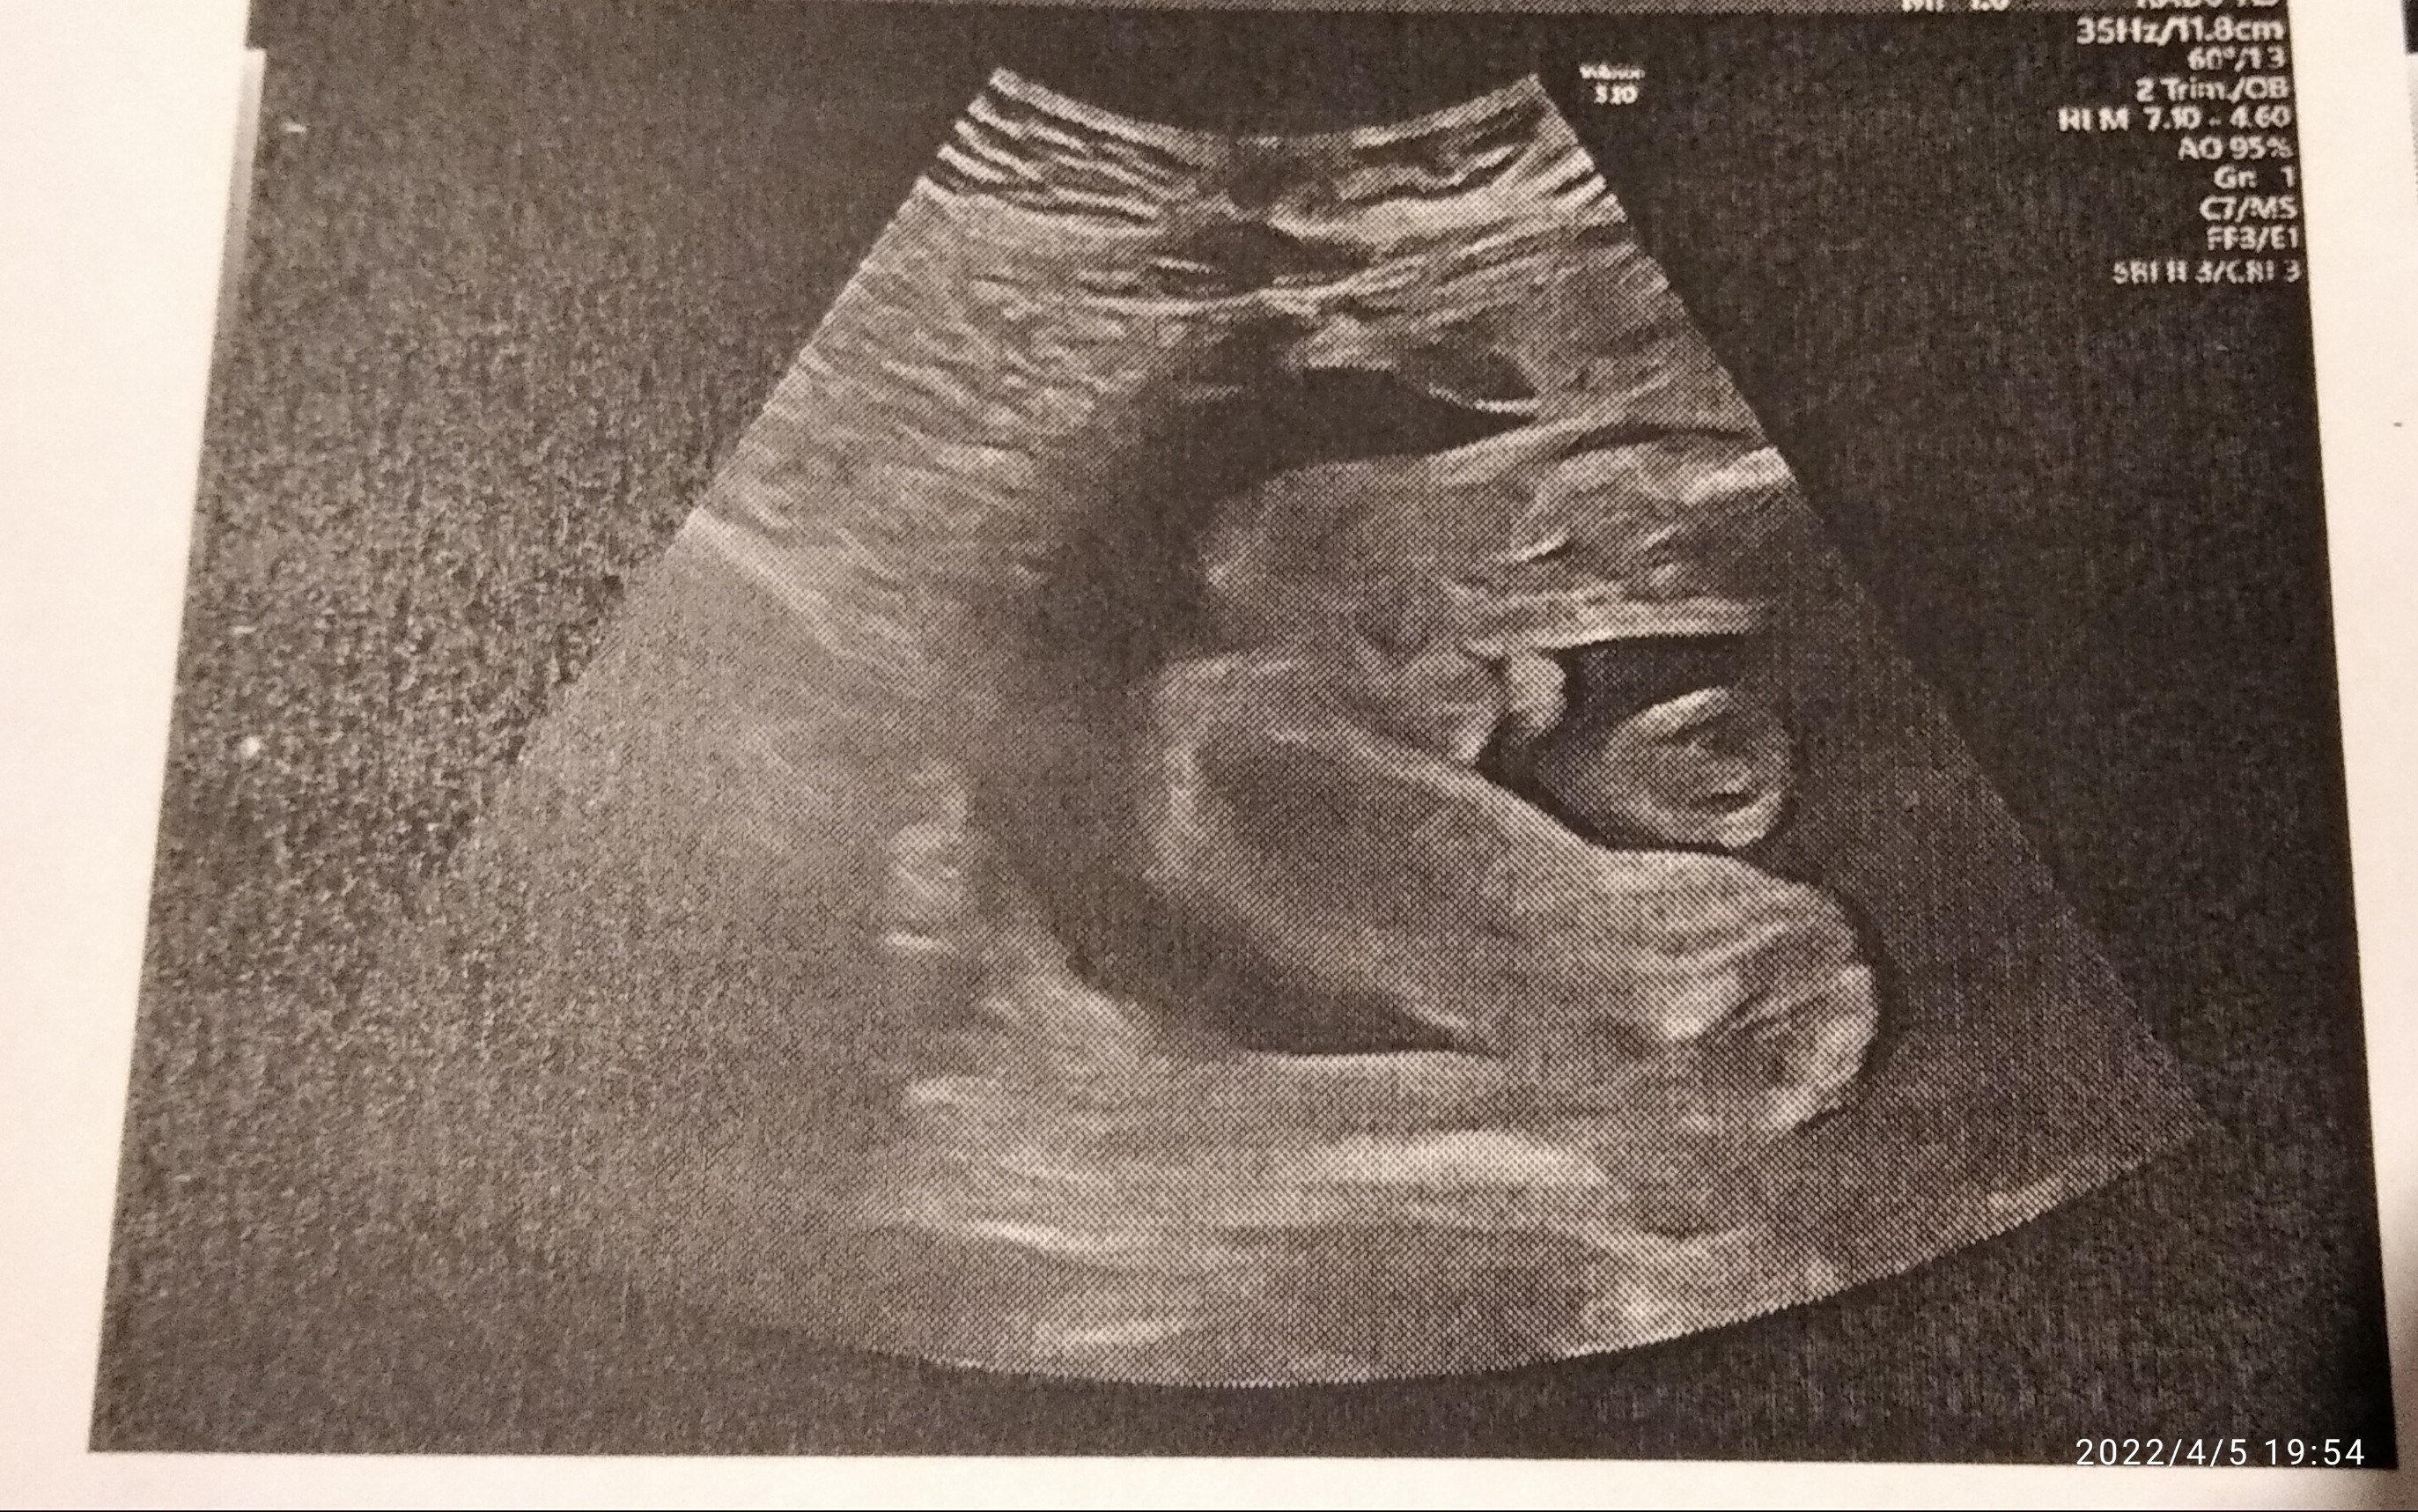

ja za to mimo tego że tutaj na moim zdjęciu niby nie widać pisiorka to i tak w 100% będę pewna kto jest po prenatalnych w 30tcTakteraz już nie ma żadnych wątpliwości

To trzymam kciuki żeby było po Twojej myślija za to mimo tego że tutaj na moim zdjęciu niby nie widać pisiorka to i tak w 100% będę pewna kto jest po prenatalnych w 30tc![]()

Chłopca już mam 5 lat w czerwcu kończy wiec bardzo bym się ucieszyła jeśli to faktycznie dziewczynka aczkolwiek kto kolwiek to nie jest to i tak już kocham z całegoTo trzymam kciuki żeby było po Twojej myślia wolałabyś chłopca czy dziewczynkę? Ja już jedną córkę mam (8lat) więc z chłopca bardzo się ucieszyłam ☺